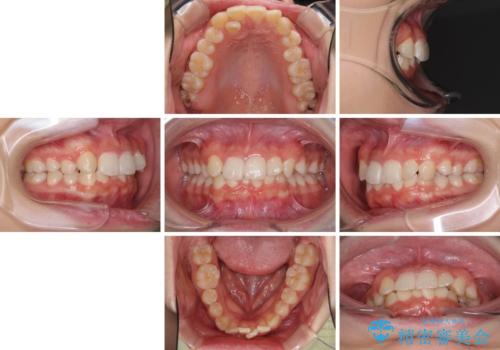

- 八重歯やデコボコをインビザラインで治療したいとのことで来院された患者様です。

インビザライン単体で治療を行うには叢生が強いと判断されたため、事前にワイヤー装置で抜歯矯正を行い、ある程度改善してからインビザラインにて仕上げていくこととしました。